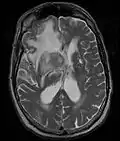

• MRI significantly underestimates extent of involvement; May appear focal on CT or MRI but parenchyma is typically diffusely involved.

• Intensely enhancing on MRI; may have a diffuse or “cotton wool” appearance on imaging.